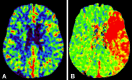

Figure (3):

Figure (3):. CT perfusion maps showing evidence of (A) preserved cerebral blood volume and (B) increased time to peak indicating big tissue at risk with small infarct territory